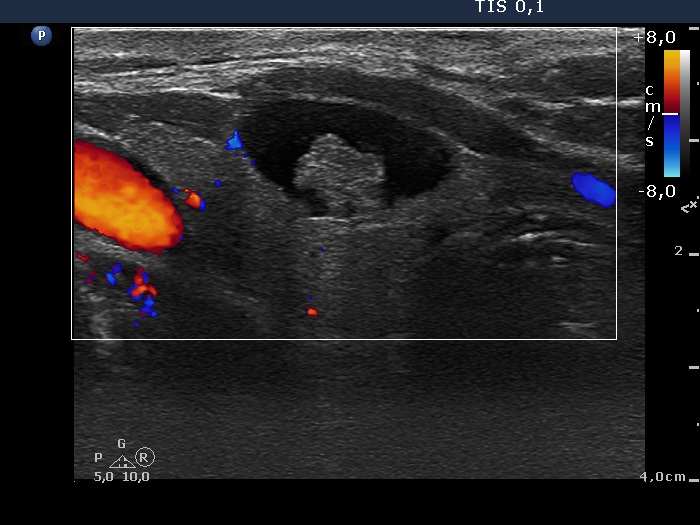

Ultrasonography. The thyroid was echonormal. There was a peripheral-type cystic nodule in the ventral part of the right lobe. The lesion had non-specific echogenic granulations. The lesion did not display vascularization on Doppler mode.